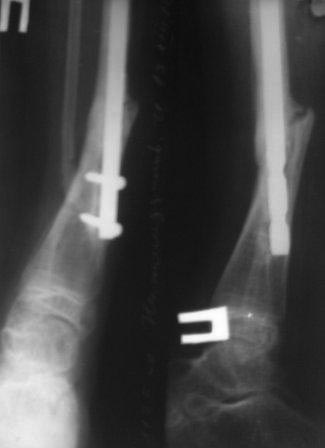

Сегодня сделал рентген, гвоздь сломался, видимо, усталостный перелом. Гвоздь и сломанная часть легко удалены, пока дистракционный остеосинтез аппаратом Илизарова, и будем постепенно исправлять деформацию. микрохирургия не доступна, оказалось, родители и повторный БИОС не могут из-за финансов,у читывая что ложный сустав не атрофичный и даже несколько гипертрофичный может продолжать аппаратное лечение? Или еще какие варианты? ,будем думать.

Контрольная Р-грамма на аппарате Илизарова после дистракции, теперь видимо придется стабилизировать аппарат после устранения остаточных деформаций.

С увважением Абдурашид.